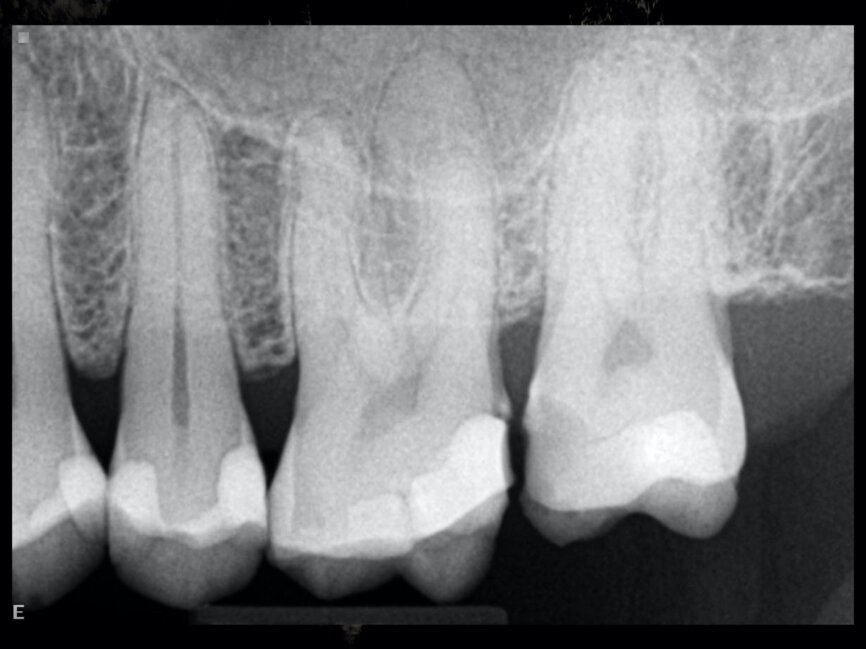

Case 2

The patient was referred for a root canal therapy of his maxillary molar. Upon creating the access cavity under a clinical microscope, we could see that the entry to the second mesial canal was at a distance from the entrance to the first (Fig. 5). Figure 6 shows the proximity of the second mesiobuccal canal to the palatal canal. Increasingly, second mesial canals are being treated in the maxillary second molar owing to the use of the microscope, ultrasonic instruments and irrigation and of course owing to the clinical knowledge regarding the use of these and owing to the use of CBCT imaging sometimes.

Figure 7 shows an immediate postoperative radiograph of the treatment. A micro-CT scan of a similar root canal system is shown in Figure 8.